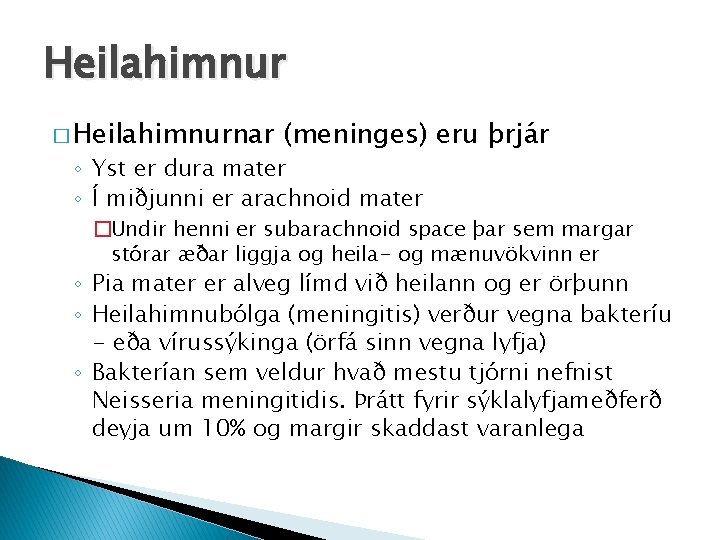

Heilahimnur � Heilahimnurnar (meninges) eru þrjár ◦ Yst er dura mater ◦ Í miðjunni er arachnoid mater �Undir henni er subarachnoid space þar sem margar stórar æðar liggja og heila- og mænuvökvinn er ◦ Pia mater er alveg límd við heilann og er örþunn ◦ Heilahimnubólga (meningitis) verður vegna bakteríu - eða vírussýkinga (örfá sinn vegna lyfja) ◦ Bakterían sem veldur hvað mestu tjórni nefnist Neisseria meningitidis. Þrátt fyrir sýklalyfjameðferð deyja um 10% og margir skaddast varanlega